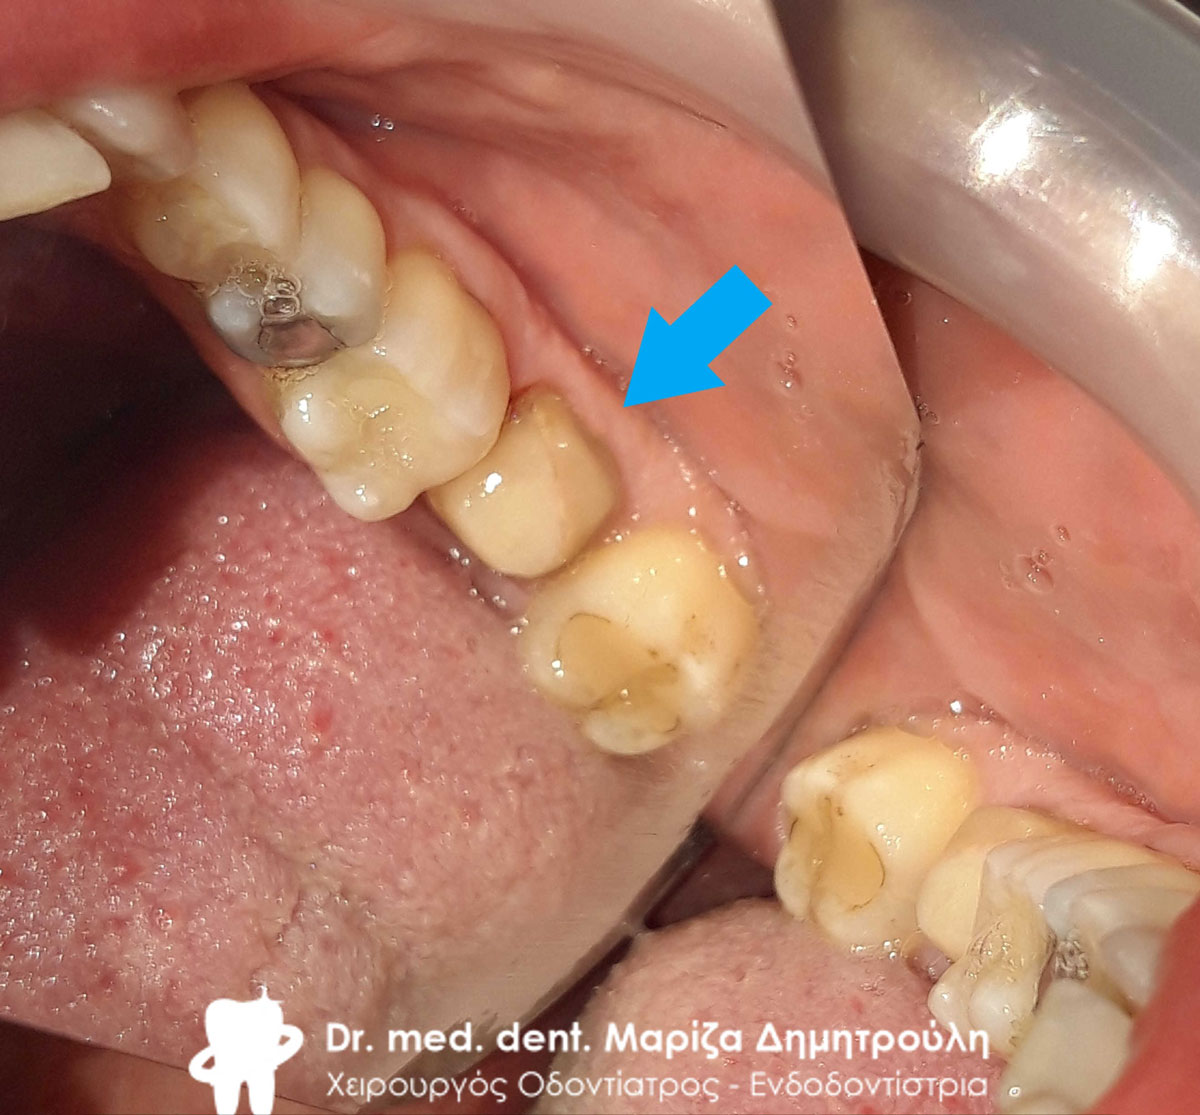

Ανασύσταση του δεύτερου γομφίου και αρχική κλινική εικόνα του τρίτου γομφίου